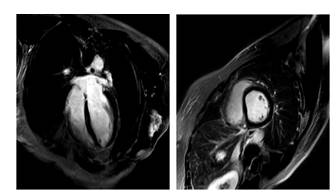

◆2016/1/27 心脏 MRI: 心肌灌注正常,心肌无延迟强化

◆UCG: LVDd 5.7cm, LAD3.9cm, LVEF 50%, 轻中度二闭

◆UCG: LVDd 5.6cm, LVEF 53%

◆UCG: LVDd 5.65cm, LAD3.9cm, LVEF: 50%